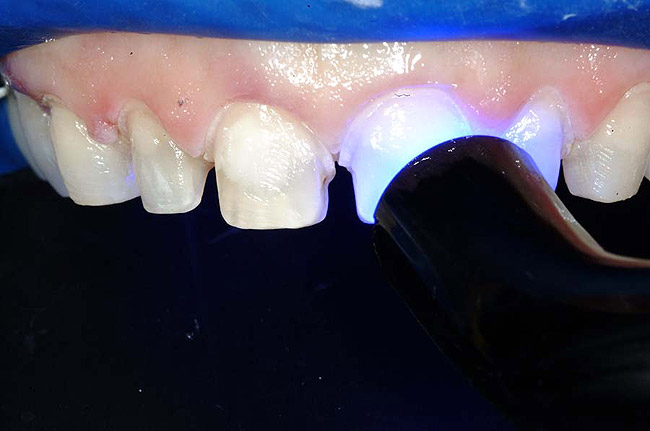

Figure 6 through Figure 8 An adhesive bonding agent (OptiBond® Solo Plus™, Kerr Corporation) was brushed onto the preparations for 15 seconds, per the manufacturer's directions, after which they were air-thinned for 3 seconds and light-cured for 10 seconds.

For example, before initiating the cementation process, preparations must be thoroughly cleansed (Figure 3), and adequate hemostasis and isolation should be ensured (Figure 4). Although newer generations of adhesives have been shown to be more tolerant of saliva contamination,7 proper isolation and hemostasis are still advisable because saliva and blood contamination cannegatively influence the bond strength of some bonding systems.8,9 Also,consider that resin cements are preferred for esthetic restorations, including porcelain laminate veneers.10,11 Successful use of these cements is dependent upon the incorporation of proper ceramic conditioning and tooth-surface treatment (ie, multiple-step total etch or self-etch adhesive)(Figure 8');" rem="#ip:figure5 through Figure 8">Figure 5 through Figure 8) to avoid incompatibility issues with the chosen cement and/or enhance the mechanical interlocking that occurs between the porcelain/resin-cement/tooth interfaces.10-13

Once the cement has been selected and loaded into the restorations (Figure 9 and Figure10), care must be taken to observe and account for the thickness of the veneers themselves. When light-cured composite cements are used for all-ceramic veneers, the curing time should be increased when activating through porcelain thicknesses of 0.5 mm to 2 mm.16,17 One study in particular suggests that the polymerization of light-cured composite resin luting agents cannot predictably be accomplished through a restoration exceeding 2 mm in thickness if the exposure to the curing light is 90 seconds or less.18 Additionally,curing times may need to be adjusted based on the wavelength of light and the type of light source used (eg, plasma arc light, high-intensity halogen light,conventional halogen light), because light intensities can vary and affect the time necessary to achieve thorough polymerization of the luting cement (Figure11).19-22 With conventional halogen curing units, there may be insufficient light transmission through thicker veneers for adequate light polymerization.22 Also, the curing efficiency of plasma arc light units for curing resin composites under porcelain laminate veneers was shown to be lower compared to the conventional polymerization units tested.21Porcelain opacity, however, has been shown to not have a significant effect on the micro-hardness or bond strengths achieved after polymerization with different types of curing lights.23,24